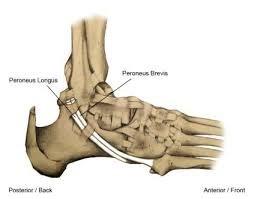

SPLATT (Split anterior tibial tendon transfer)

De SPLATT, of ½ tibialis anterior transpositie, omhelst het verplaatsen van de helft van de tibialis anteriorpees naar de buitenzijde van de voet. Hiermee wordt wederom een kracht van de binnenzijde naar de buitenzijde van de voet verplaatst om de balans te verbeteren. De verplaatste pees wordt meestal vastgehecht aan de peroneus tertiuspees die aan de voor-buitenzijde van de enkel/voet loopt en de voet naar buiten en omhoog beweegt.

Figuur 3: De tibialis anteriorspier. Bij het streepje op het linkerplaatje komt een litteken waar de helft van de pees wordt losgemaakt. Dat stukje pees “tunnelen” we naar net boven de enkel (2e plaatje). Dan verplaatsen we dat stukje pees naar de buitenzijde van de voet (streepje op 3e plaatje) en hechten deze vast aan de peroneus tertiuspees. Op het meest rechtse plaatje staat de eindsituatie waarbij de pees voor de helft naar de buitenzijde van de voet is verplaatst en de balans is veranderd.